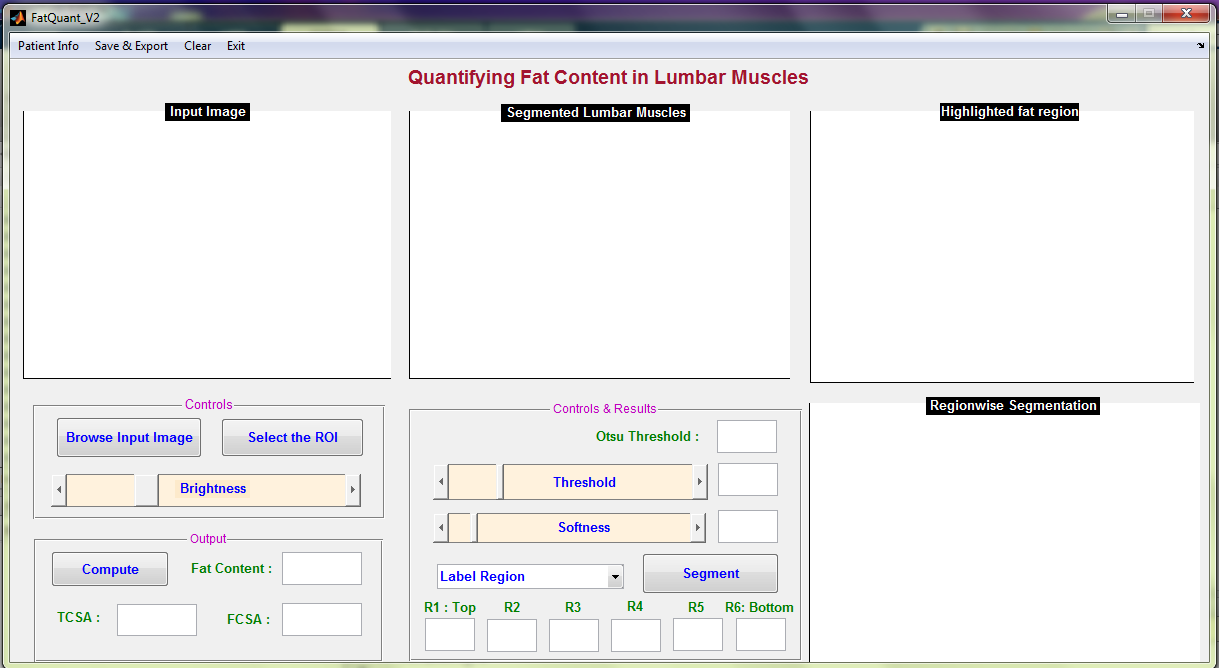

2.2 Interactive segmentation tool

A standalone Graphical User Interface (GUI) shown in Figure 1 using Matlab R2010a was developed with the essential interactive controls. Initially the GUI, allows the user to select an input image. Then the user can define the region of interest (ROI) by plotting a mask using the livewire (intelligent scissors) interactive segmentation technique [21]. Once the mask is created interactively, the ROI is segmented and the grayscale image is displayed in the GUI. The global threshold to convert the grayscale image into a binary image is calculated using Otsu’s method [28]. By default the threshold value is set at Otsu’s threshold and the softness value is set at 0.2 (this value is based on empirical investigation). The softness value is mainly used for improving the visual clarity of fat regions by smoothing the edges of fat regions. For incremental variation of softness value in the steps of 0.1 from values 0 to 0.5, the fat percentage varies from 0.2 to 2 and the cross sectional area varies upto 3 . Initially, with pre-defined threshold and softness, the fat regions are identified from the segmented lumbar muscle and displayed in the GUI. Based on visual inspection, suitable values for threshold and softness can be fixed by adjusting the ‘Threshold’ and ‘Softness’ sliding controls respectively. The ‘Brightness’ sliding control allows the user to adjust the brightness of the input image for better visualisation.

The total fat content percentage, total cross-sectional area (TCSA) and functional cross-sectional area (FCSA) in can be calculated at any stage by pressing the ‘Compute’ button. The computation of fat content percentage, TCSA, and FCSA is performed in line with the previous studies [5, 2, 4, 25].

By using the drop down menu ‘Label Region’ the user indicates the region of interest. The list of regions included in the menu are Right Erector Spinae muscles, Left Erector Spinae muscles, Left Lumbar Multifidus Muscles, Right Lumbar Multifidus Muscles, Right Psoas Muscles, and Left Psoas Muscles.

The Erector Spinae (ES) Muscle is sub-divided into six fragments at equal intervals with reference to the center of spinal column and fat in each region is quantified. The center of spinal column is automatically detected for a given input image. The region wise quantification of fat in the ES muscles, either on left or right side of the spinal column, is carried out by selecting ‘Segment’ in the GUI. The ES muscle fragments are labelled R1 to R6 from top to bottom respectively, the fat percentage in each region is computed and displayed in the GUI.

The GUI was iteratively developed based on feedback from experts. The GUI includes the Otsu’s threshold set as the initial reference, variable-selection of threshold and softness levels, computation of total and functional cross-sectional area, region-wise fragmentation of the ES muscle with reference to the centre of spinal column, which were based on experts opinion.